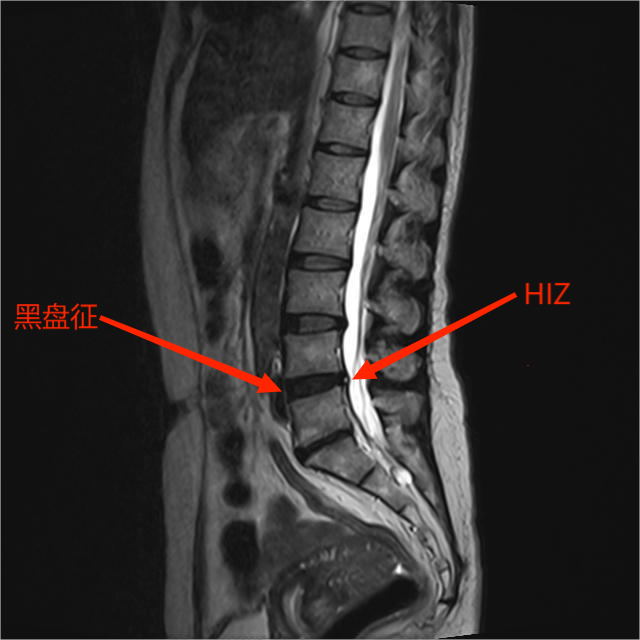

1.排他:腰痛持续 >6 个月,正规保守治疗(药物+康复)>3–4 个月无效;X 线、CT 排除滑脱、不稳、椎管狭窄;MRI 无明显神经根受压

2.MRI:T2像显示退变椎间盘低信号(黑盘征)及纤维环后方高信号区(HIZ)

3.椎间盘造影:阳性表现为椎间盘造影时诱发、复制下腰部疼痛,并且椎间盘造影显示纤维环撕裂。